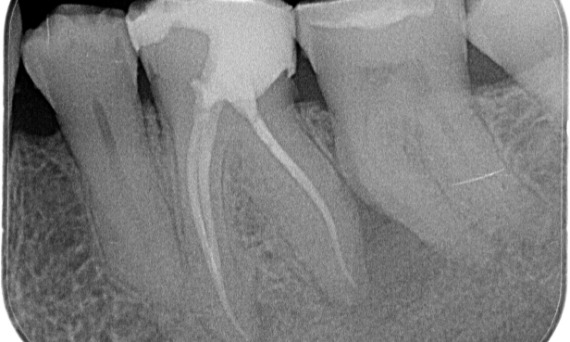

14ヶ月の経過観察を経た、根が長く石灰化した複雑な症例

"患者とプロセスを中心とした成功。"- Cowie医師

ビフォー:主に遠位根に関連する根尖周囲の放射線透過性、および中間根の硬膜喪失。

アフター:TruNatomyがこの症例で選択されまたのは、カリエスを活用したアプローチを可能にし、特に最小限の修復しか施されていない中顎側面の歯頸部周囲象牙質の保存に重点を置いているためです。